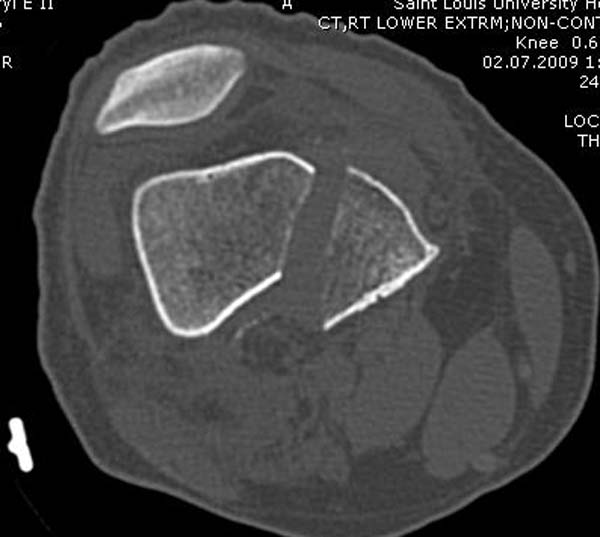

Диагностическая ошибка происходит, когда игнорируется правила обследования внутрисуставных переломов. Вместо полного обследования, включая КТ, ограничиваются рентгенограммой, и то в одной проекции!

Nork et al, J Orthop Trauma, 87:564, 2005 доложили, что над- и чрезмыщелковые переломы бедра в 38% имеют линию перелома в корональной плоскости!

Спасибо большое за советы! Добавляю некоторые КТ снимки. Перелом коллеги не диагностировали, видимо, расценив костную травму как повреждение задне-латерального комплекса коленного сустава. Отпишусь по результату выполненной операции.